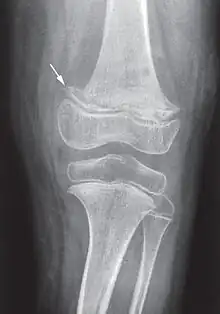

X-ray of the knee joint (arrow indicates scurvy line)

While many animals produce their own vitamin C, humans and a few others do not.[2] Vitamin C, an antioxidant, is required to make the building blocks for collagen, carnitine, and catecholamines, and assists the intestines in the absorption of iron from foods.[2][4][5] Diagnosis is typically based on outward appearance, X-rays, and improvement after treatment.[2]

Diagnosis is typically based on physical signs, X-rays, and improvement after treatment.[2]